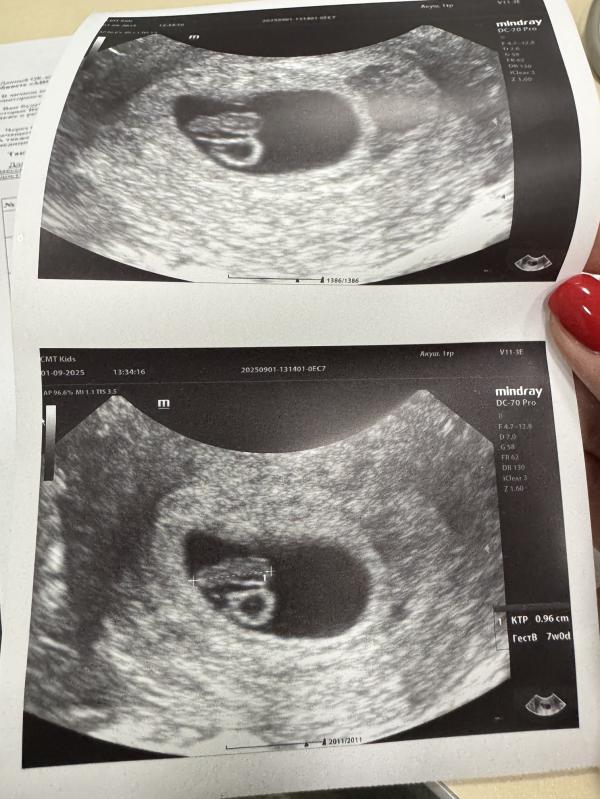

Мне надо восстановить хронологию событий, раз я не стала вести свою страничку с самого начала. УЗИ проходила каждые 2 недели. История развития маленького человека🥰 Последнее фото со скрининга на флотской, лялька с характером, совсем не давалась смотреть и фоткаться😁